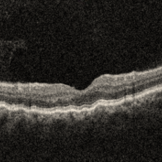

RE-OCT in Choroidal Detachment

A 52 year old male came with chief complaints of diminution of vision in RE since past 15 days. He gave history of ( RE ) cataract surgery + IOL about 2 months ago. His vision was 6/9 in RE and PL + ve, PR inaccurate in LE. His IOP was 10 mm of Hg in RE and 20 mm of Hg in LE.